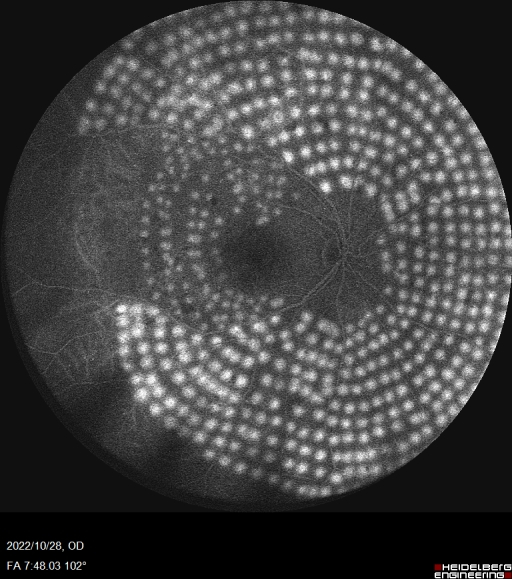

眼底血管造影是眼科临床上非常重要的检查方式,广泛应用于眼底血管疾病。海德堡共焦激光同步血管造影系统采用独特的共焦激光造影,只接受共焦平面的发射光,没有散射光干扰,可以获得高分辨率、高对比度的造影图像。同时基于共焦激光逐点扫描的特点和激光的高准直性,Spectralis HRA在小瞳下也可以获取高质量图像。可以同步进行FFA和ICGA造影,一次拍摄可将视网膜与脉络膜的血管造影实时同屏显示,方便临床医生进行同步对比观察,为诊断提供更全面和精准的信息。

此次合肥普瑞眼科医院引入的海德堡 Spectralis HRA共焦激光同步血管造影系统可配备有“天幕”102°超广角镜头,是造影设备的全新升级。102°超广角造影图像的观察范围更广,有效涵盖周边眼底,可以更早的发现早期糖尿病视网膜及一些血管性疾病的周边部改变,对于控制患者病情发展,减少视力损害意义重大。同时Spectralis HRA还具有动态造影的独特功能,每秒钟可以获取16帧高清图像,全程记录血管充盈过程,不遗漏重要细节。

10月28日,眼底病专科副主任张思伟利用海德堡 Spectralis HRA共焦激光同步血管造影系统顺利完成首例患者广角眼底血管荧光造影检查,为眼底病患者后续相关治疗提供有力支持,标志着合肥普瑞眼科医院眼底病专科诊疗水平再上新台阶。未来,合肥普瑞眼科医院将始终秉承“用爱传递光明”的理念,坚持以患者为中心,优化医院重点特色专科建设,全面提升医院各项诊疗服务水平,为人民群众的眼健康保驾护航!